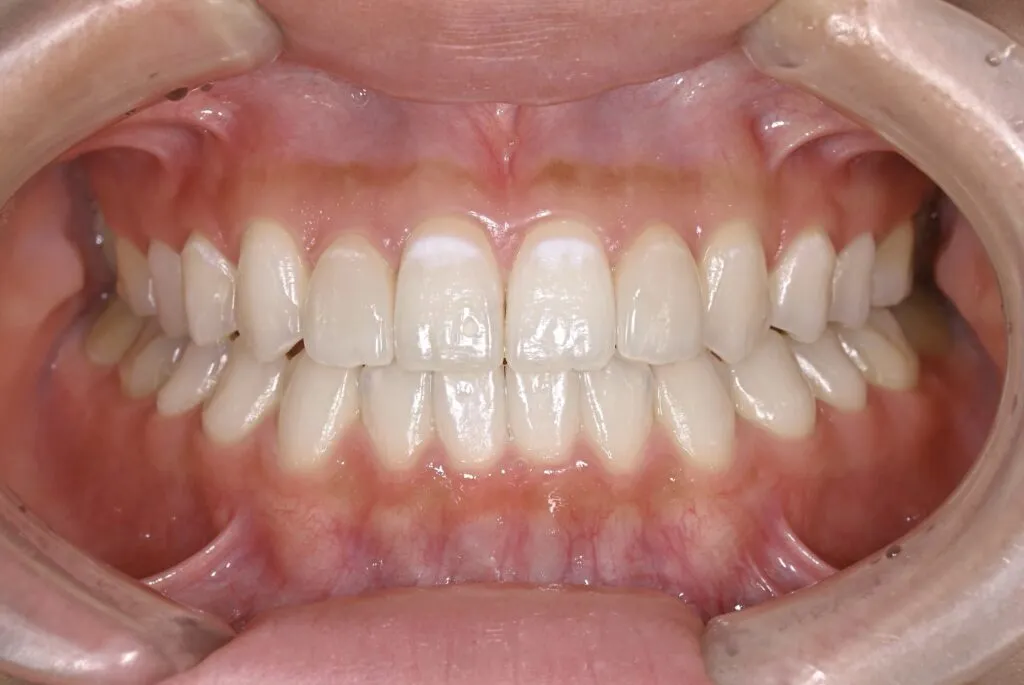

[症例2]

治療前は臼歯部は保険の冠のため金属色が目立ちます。上顎の前歯はセラミックですが、古いタイプの治療法ため裏側に金属が露出しています。

矯正治療後に部分被せも含めて全てセラミックで治療しました。

右下6番は歯を真ん中で分割して2本の冠が入っていましたが、抜歯してインプラントが入っています。

上下顎とも金属色の見えない美しい歯並びになりました。

- 治療期間:約1年

- 治療費:240万円

- 治療回数:26回